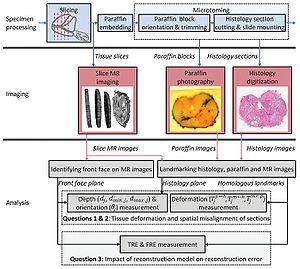

- 5.12 3D Prostate Histology Image Reconstruction: Quantifying the Impact of Tissue Deformation and Histology Section Location